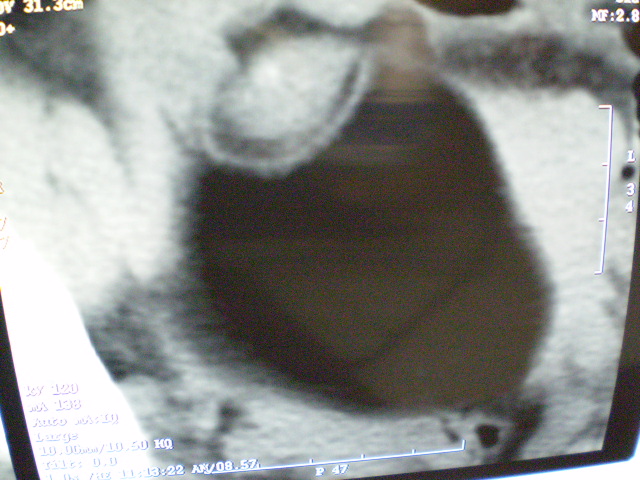

f 60y,b超提示脂肪瘤.[img][/img]

右侧附件囊性畸胎瘤,三种组织均见.

右侧附件囊性畸胎瘤.

那个高密度灶形状好象牙齿。典型,收藏了

脂肪密度肿块,内可见团块状影,典型皮样囊肿

的确比较典型的畸胎瘤!不过,应该确切的说是盆腔畸胎瘤,右侧附件来源的可能性比较大。